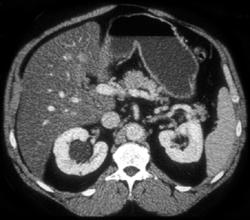

Antral Carcinoma